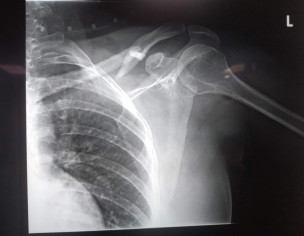

My wife has suffered an accident and fractured her left clavicle. The ortho specialist said there will be no intervention, and just put a tight 8 bandage around her shoulder and instructed it to get rebandaged twice a week to make sure it remains tight. 6 weeks recovery time has been suggested. X-rays are being attached for reference. Please advice if what has been suggested is appropriate or something more needs to be done?

Thnx for opinion,there are 2 xray films,no date of exposure is mentioned on them,in both xray films,there is difference in fracture ever most of clavicle fractures r managed non operatively,so is this one u said,tight 8 bandage,this is not tight but figure 8 bandage.4 weeks r sufficient to put this fracture in such u have consulted orthopaedic surgeon,then u must follow periodically as he advised y u felt the need of 2nd opinion?

Dr. Dileep Kumaar: The X-rays were taken an hour after the accident took place. Both X-rays at the same time, but with different position of the hand... Need for 2nd opinion arose because someone told me that the figure 8 bandage is not needed in cases like these.